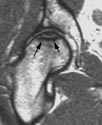

MRI's of Femoral Heads

diagnosed with Osteonecrosis

Small

Lesion

Large